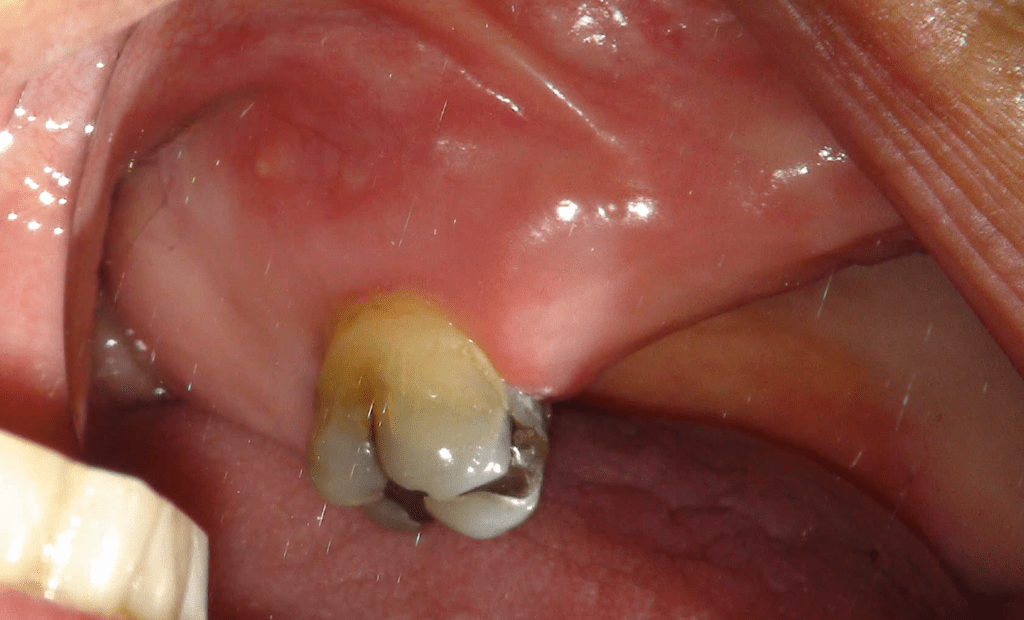

Fisura, remoción amalgama para explorar